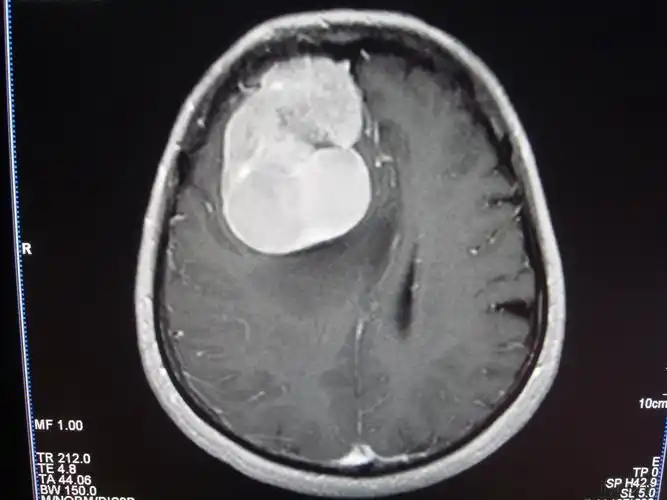

读片丨女30岁间断性头痛颅脑ctmri